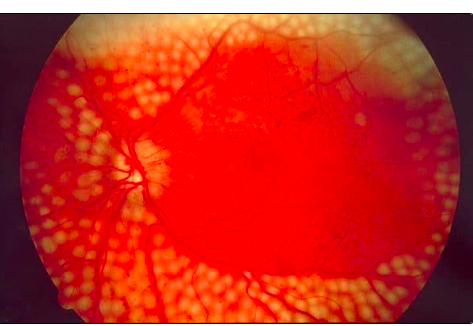

What is depicted in this image? [1]

Proliferative diabetic retinopathy:

extensive vitreous haemorrhage obscuring most of fundus (white circle)}